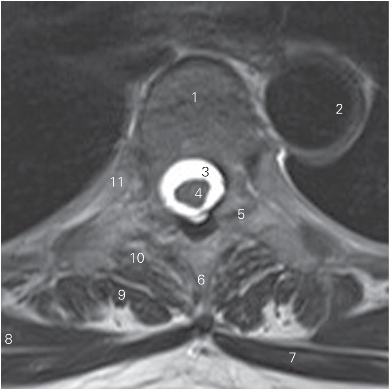

图2-5 经第5胸椎椎体的横断层MR T2加权图像

1 第5胸椎体 5th thoracic vertebral body 2 胸主动脉 thoracic aorta

3 蛛网膜下隙 subarachnoid space 4 胸髓 thoracic cord

5 关节突关节 zygapophyseal joints 6 棘突 spinous process

7 斜方肌 trapezins 8 竖脊肌 erector spinae

9 多裂肌 multifidus muscle 10 回旋肌 rotatores

11 第5肋 5th rib